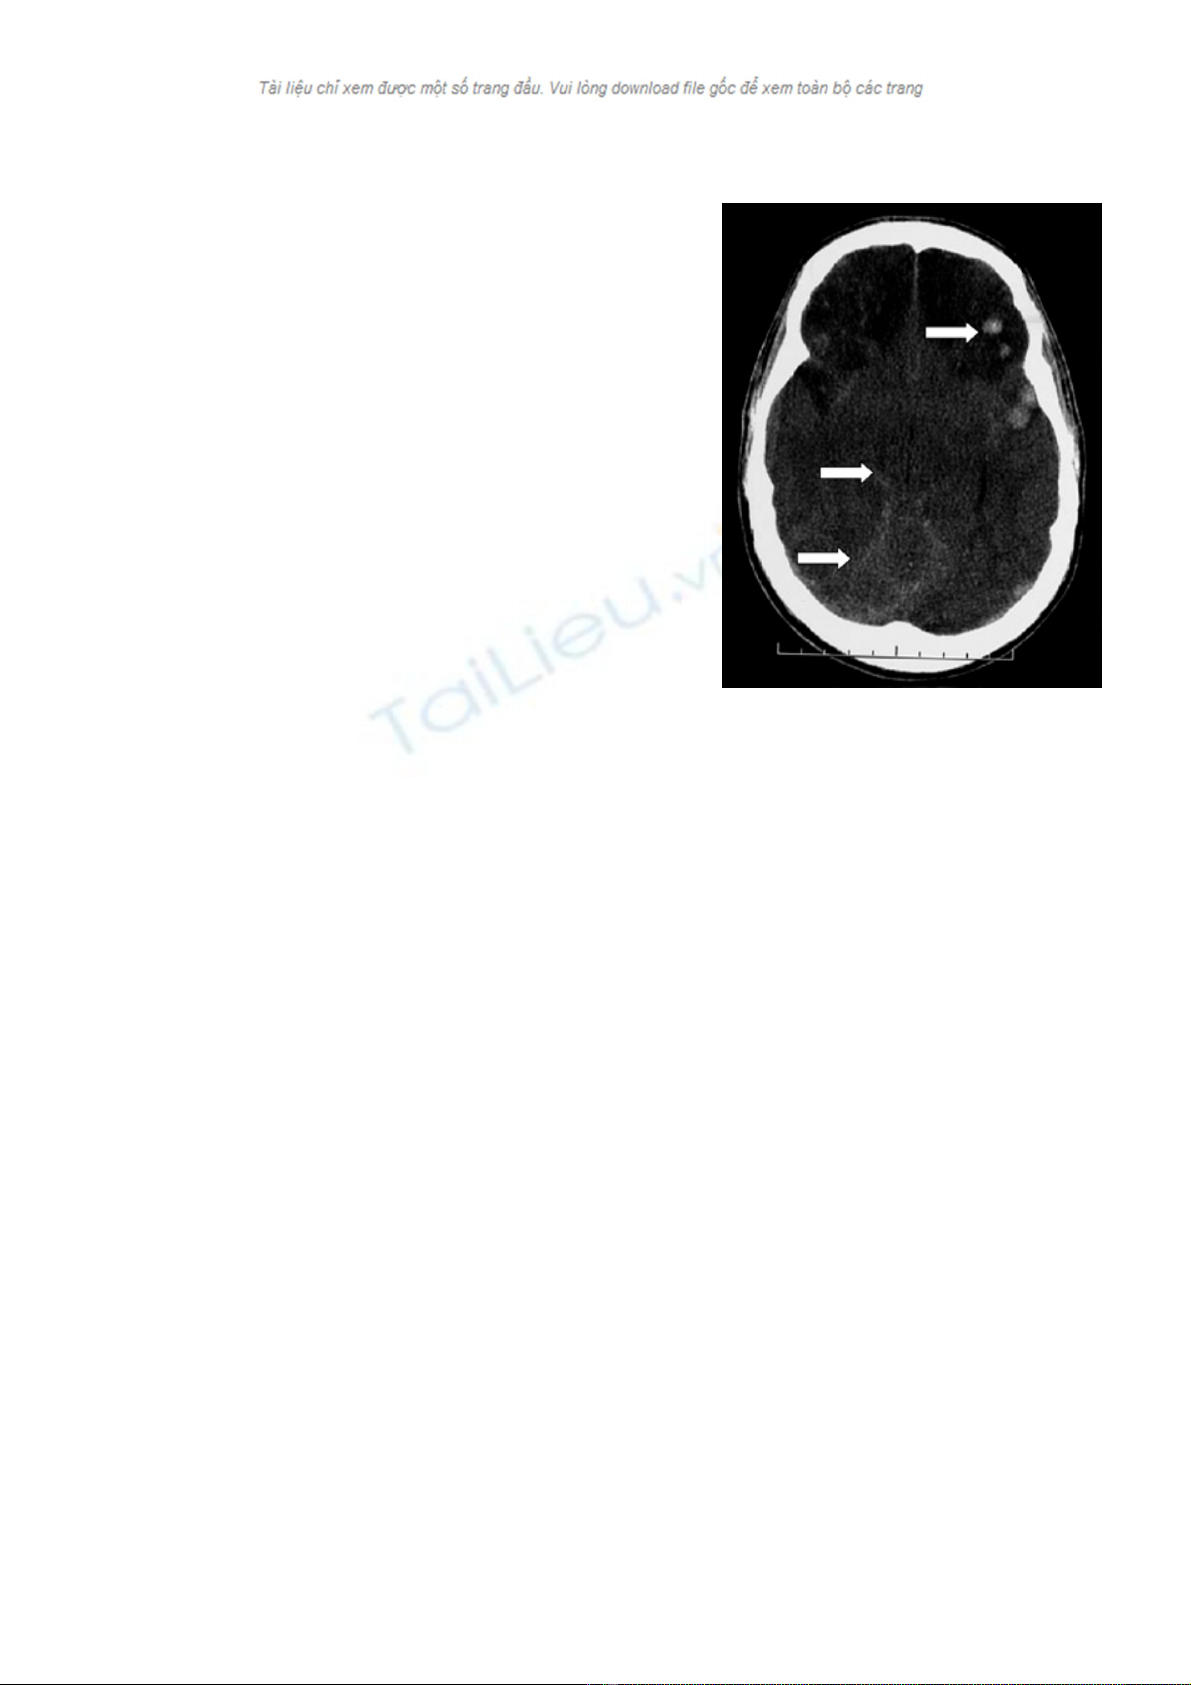

Hình ảnh CT Scan đầu gợi ý có tăng ALNS (hình

Có khối choán chỗ đáng kể trên lều, đẩy lệch

đường g

+ Các rãnh vỏ não bị xóa, các bể dịch não tủy bị

sậ

choán chỗ

Não thất giãn khi đường đi củ

tắc.